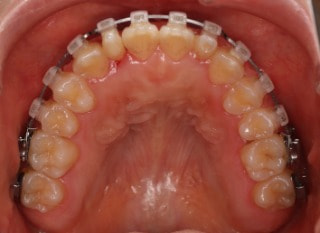

治療開始時

治療開始から25ヶ月後